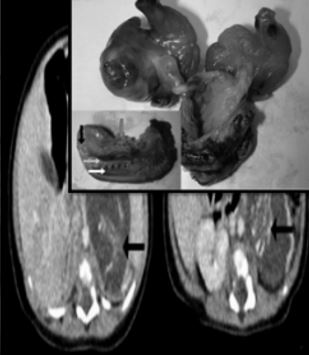

Seorang bayi perempuan yang baru berusia tiga bulan telah disahkan ’hamil’ apabila di dalam perutnya mengandungi satu lagi janin.

Janin yang berada di dalam perut bayi berusia tiga bulan itu dikatakan berusia 10 minggu kandungan.

Semasa awal kandungan, ibu kepada bayi itu telah disahkan hamil kembar dua.

Namun, setelah selamat melahirkan dua bayi tersebut, dia telah dimaklumkan bahawa terdapat seorang lagi bayi di dalam perut anaknya itu.

Menurut Jurnal Perubatan Hong Kong, kejadian tersebut dikatakan amat jarang berlaku dan ianya merupakan kes pertama di sepanjang 500,000 jumlah kelahiran di negara itu.

Pakar obstetrik dan ginekologi, Dr. Yu Kai Man berkata, amat sukar bagi mereka untuk mengesan kewujudan janin tersebut pada awal kandungan kerana saiznya yang terlampau kecil.

Pihak hospital kemudian masih belum menentukan rawatan selanjutnya yang akan dilakukan kerana perlu mengambil kira aspek keselamatan dan nyawa bayi tersebut.